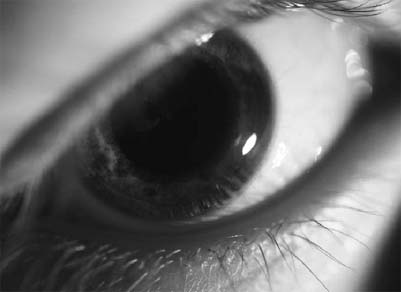

Glaucoma is a disease characterized by elevated intraocular pressure, optic nerve damage, and subsequent impaired vision. Glaucoma is one of the leading causes of adult blindness in the United States and worldwide. Risk factors include increased age, African-American race, and family history in a first-degree relative. The main types of glaucoma include primary open angle glaucoma, angle closure glaucoma, and congenital glaucoma. Primary open angle glaucoma is the most common form of glaucoma and occurs in 0.5 to 2.1 percent of the population over the age of 40. It is caused by a resistance to flow of aqueous humor. Aqueous humor is produced in the ciliary body and drained by the trabecular meshwork. Dysfunction of the trabecular meshwork leads to a disruption in the normal flow of aqueous humor. This results in an increase in the pressure of the eye and damage to the optic nerve. The increased pressure causes a decrease in the blood supply to the nerve and thus damage to the nerve. Over time, due to the damage to the nerve, patients will gradually lose peripheral vision. In advanced cases, the vision loss can lead to absolute blindness.

Angle closure glaucoma results from the peripheral iris, or colored part of the eye, blocking the trabecular meshwork. The angle closure leads to a rise of the in traocular pressure from its normal level (10 to 21 mm Hg) to 30 mm Hg or more. This results in an increase in aqueous fluid inside the eye causing damage to the optic nerve. Prodromal symptoms occur as transitory attacks during which time patients may experience symptoms of decreased vision, eye pain, halos around lights, headache, nausea, and vomiting.

Another important type of glaucoma is congenital or infantile glaucoma. Congenital glaucoma has an incidence of 1 in 10,000 births with an increased incidence in males. The exact cause is unknown but appears related to a maldevelopment of the aqueous humor drainage system. Signs and symptoms include enlarged cornea (buphthalmos), photophobia, and tearing. Prompt surgical intervention offers the best method of controlling the intraocular pressure and long-term preservation of vision.

For the adult patient, the first signs of glaucoma include gradual loss of peripheral vision. Patients with angle closure glaucoma may present with pain and colored halos, but with primary open-angle glaucoma, patients may be asymptomatic until late in the disease. Glaucoma screening involves a complete ophthalmic history and examination, including evaluation of intraocular pressures, optic nerve, visual fields, and gonioscopy (evaluation of the drainage system of the eye). Intraocular pressure in most individuals ranges between 10 and 21 mmHg, with an average of approximately 16 mmHg. Patients with pressures above 21 are suspicious for glaucoma. Intraocular pressures can fluctuate throughout the day, so pressure levels cannot be the only screening tool for glaucoma.

During examination, the optic nerve is also observed. The optic nerve is examined by comparing the cup to disk ratio. A central depression exists in the optic nerve called the cup. An increase in the size of the cup relative to the rest of the nerve signifies glaucomatous damage. Physical examination should also include gonioscopy. Gonioscopy consists of a special lens placed on the eye that allows visualization of the trabecular meshwork, peripheral iris, cornea, and presence of angle closure. For patients with glaucoma, management includes intraocular pressure checks every three to six months, visual field examination every six to 12 months, gonioscopy and optic nerve evaluation yearly.